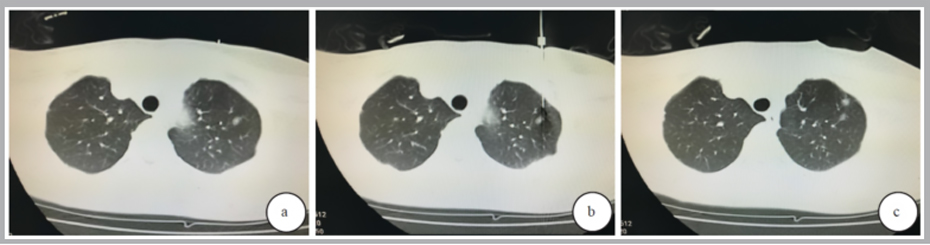

图例:女,36 岁,肺微浸润性腺癌。右下肺外基底段磨玻璃结节(箭),直径约7mm(A);CT定位穿刺针位置(箭,B);快速医用胶形成的小结节(箭)、磨玻璃结节(箭头,C);右下肺楔形切除组织,病灶(箭头)直径约6mm,灰红结节(D)